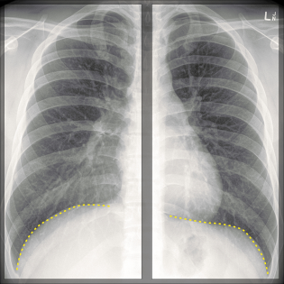

The ring is denoting the location of?

Explanation: ***Tricuspid valve*** - The image likely displays a **cardiac outline** on an X-ray, and the ring points to the typical location of the **tricuspid valve** within the right side of the heart. - The tricuspid valve separates the **right atrium** from the **right ventricle**. *Pulmonary valve* - The pulmonary valve is located anterior and to the left of the tricuspid valve, separating the **right ventricle** from the **pulmonary artery**. - Its position is generally superior and more towards the midline compared to the ring's location. *Mitral valve* - The mitral valve is situated on the **left side of the heart**, between the **left atrium** and **left ventricle**. - Its location is distinctly different from the highlighted area. *Aortic valve* - The aortic valve is located between the **left ventricle** and the **aorta**, typically found superior and central in relation to the cardiac silhouette. - This position is away from the area indicated by the ring.